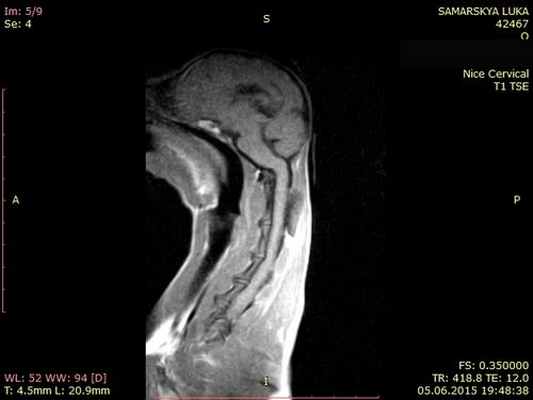

МРТ исследование пациентов с атланто-аксиальной сублюксацией

МРТ обеспечивает превосходное разрешение при исследовании нервной паренхимы и позволяет выявить другие патологии мозга, такие как дорсальную компрессию С1-С2, атланто-окципитальный оверлепинг, Киари и прочее.

Той терьер с атланто-аксиальной нестабильностью